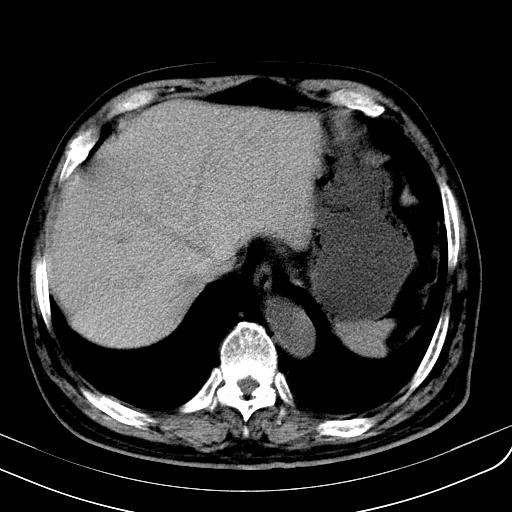

胃底靠近胃大弯处可见一圆形软组织影,直径为3.45cm,ct值约为30.1hu

请会诊!!!